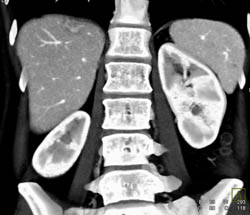

Focal Nodular Hyperplasia (FNH)